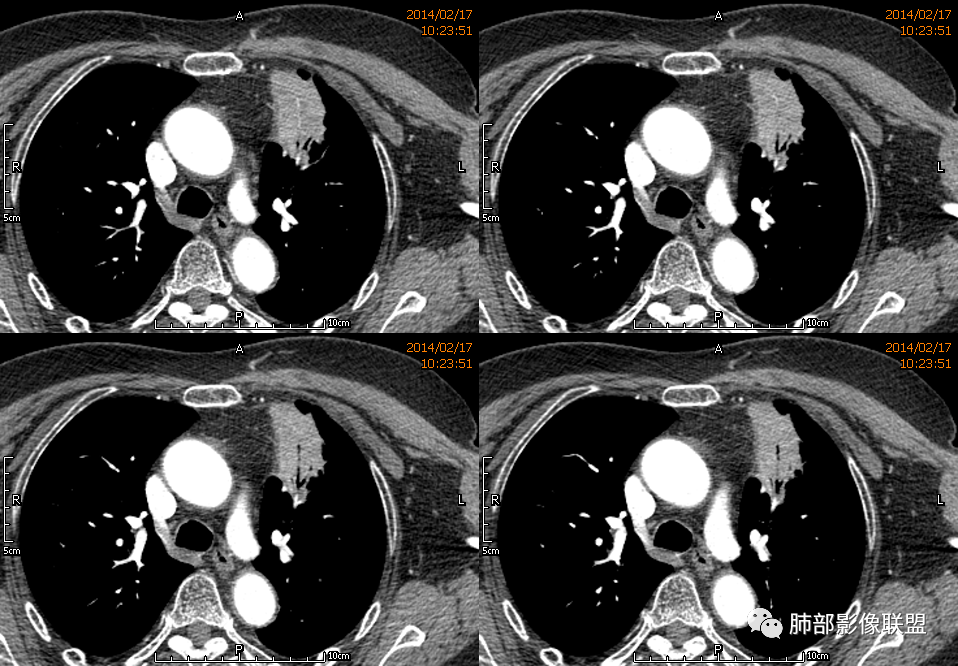

红星: 老年女性,咳嗽咳痰10天,痰中带血4天。左肺上叶前段胸膜下肿块影,沿支气管方向走行以膨胀生长为主,局部有收缩改变,支气管血管绝断,中间有小片状的坏死及小的空洞影,增强扫描病灶明显的强化,病灶周围网格状的小叶间隔增厚。拟左肺上叶前段浸润型腺癌并癌性淋巴管炎。鉴别诊断结核肉芽肿。

傅昌瑜: 老年女性,咳嗽咳痰10天,痰中带血4天。左肺上叶前段胸膜下肿块影,沿支气管方向走行,膨胀生长为主,局部边缘似有收缩改变,中间有小片状的坏死,支气管进入,增强扫描病灶明显的强化,血管走形较自然(血管漂浮征?),病灶周围网格状的小叶间隔增厚。考虑淋巴瘤可能性大,注意鉴别炎性肉芽肿及肺腺癌。

水晶石头: 患者老年女性,咳嗽咳痰10天,痰中带血4天余。查血常规白细胞低;肿瘤标志物、凝血功能正常;血生化:蛋白低;C反应蛋白、血沉稍升高。胸部CT:左肺上叶前段胸膜下沿气管支气管走形肿块影,长轴与胸膜平行,见分叶、毛刺、支气管截断、空泡征象。增强明显强化,且见血管造影征及病灶内小灶低密度坏死区。左肺上叶尖后段见一结节灶。综合考虑恶性病变可能大,腺癌或淋巴瘤可能。鉴别诊断肺脓肿。

尘缘: 老年女性,咳嗽咳痰10天,痰中带血4天,白细胞及中性粒明显减低,轻度贫血。影像表现:左上叶肿块,边缘膨隆,局部平直,支气管稍扩张,进入后远端堵塞,内见小空洞及不规则坏死区,增强后强化明显,坏死边界较清,并见环状强化区,内部血管走行自然,周围见小叶间隔增厚呈大网格征。初步诊断:慢性炎性伴脓肿形成及肉芽组织增生。鉴别淋巴瘤及腺癌,先抗炎治疗后复查或直接穿刺明确。

王崇军: 老年女性,咳嗽咳痰10天,痰中带血4天。左肺上叶前段胸膜下 肿块影及段形态密度增高影,沿支气管方向走行,膨胀生长为主,局部有收缩改变,支气管进入并闭塞,中间有小片状的坏死及小的空洞影,空洞漂浮在坏死边缘,增强扫描病灶明显的强化,坏死边界清楚,似乎有轻度强化环,病灶周围网格状的小叶间隔增厚及小结节影,外侧胸膜呈糊墙改变。考虑为肺脓肿,这么大的病灶,竟然没有发烧,白细胞低,CPR轻度升高,均与脓肿不符,所以恶性待排,短期抗炎治疗后复查,病灶没有变化,脓肿就可以排除,恶性基本可以确定。

血管走形自然

3.病灶密度不均,中央坏死液化并见气泡影,支气管及血管贴边进入,较均匀环形强化(显示多层结构),未见明确壁结节。

3.病灶易坏死液化,环形强化,支气管及血管贴边进入,“火焰”样边缘轮廓,更符合炎性块影的特点。